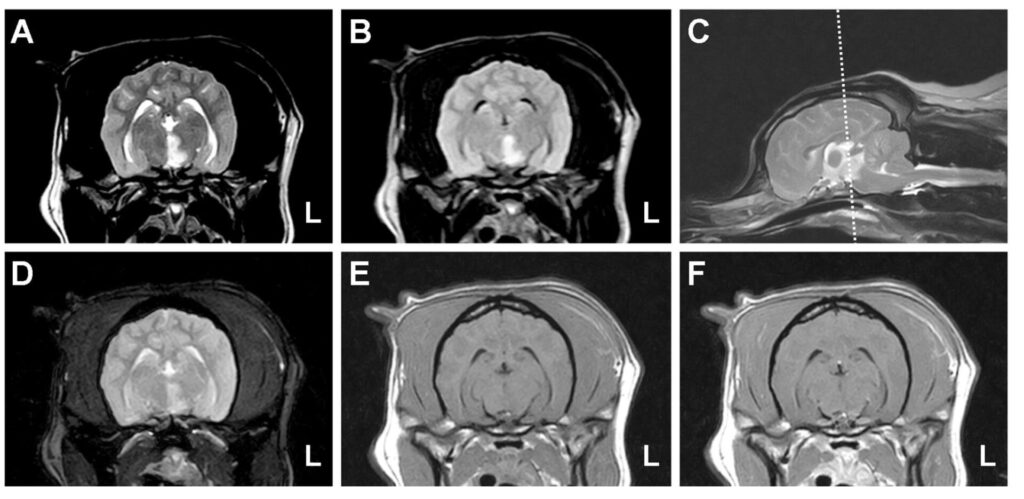

You may suspect that the patient has suffered a stroke based on the signs they are showing. Further tests, including brain imaging, will be needed to make a definite diagnosis. MRI (magnetic resonance imaging) scans can give an inside view of the brain (see caudal perforating artery image and borderzone infarct image on MRI). This diagnosis cannot be made with standard X-rays. As part of these tests, the pet will be anaesthetized, and a spinal fluid sample will be taken to check for other diseases that may cause similar signs.